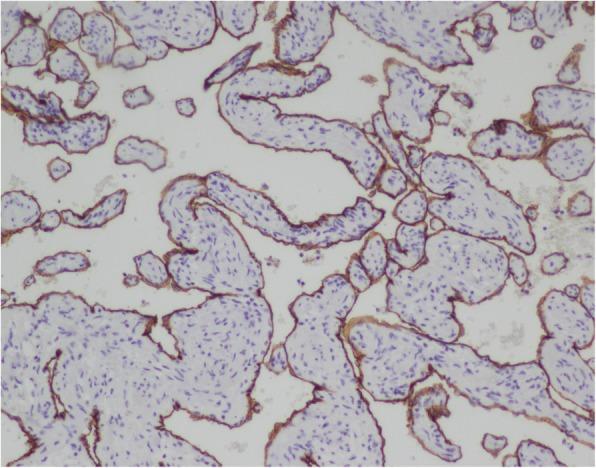

An asymptomatic 56-year-old woman was hospitalized due to a heart mass found by chest computed tomography (CT) during her annual physical examination. Coronary computed tomography angiography (CTA) disclosed a tumorous lesion, located in the left atrial roof and extended to the posterior wall of the aortic root and surrounding the left main coronary artery. However, there was no communicating branches between the hemangioma and coronary artery and no coronary artery stenosis. The tumor was excised with low-frequency electrocautery under cardiopulmonary bypass. The histopathological examination indicated the mass a cavernous hemangioma. The patient was discharged with an uneventful recovery.

一名56岁无症状女性因年度体检时胸部计算机断层扫描(CT)发现心脏肿物而住院。冠状动脉计算机断层扫描血管造影(CTA)显示一个肿瘤性病变,位于左心房顶部,延伸至主动脉根部后壁并包绕左冠状动脉主干。然而,血管瘤与冠状动脉之间无交通支,也无冠状动脉狭窄。在体外循环下用低频电灼切除肿瘤。组织病理学检查显示肿物为海绵状血管瘤。患者康复顺利出院。